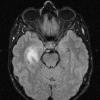

NEOPLASMS (GLIAL)

Astrocytoma, IDH-mutant, WHO Grade 2 (12)